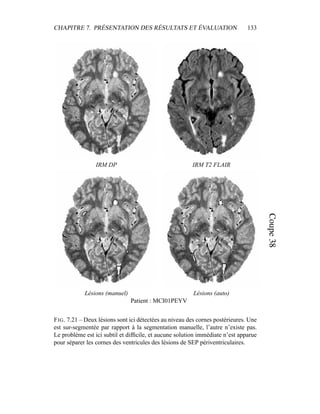

CHAPITRE 8. DISCUSSIONET PERSPECTIVES 168 Cette étude aura montré que le choix d’algorithmes simples prenant pour base l’intensité des voxels donne des premiers résultats qui peuvent servir de socle à des traitements postérieurs. La poursuite d’une telle étude et le perfectionnement de la chaîne de traitements nécessitent néanmoins une évaluation plus approfondie. L’intégration de plusieurs experts pour une évaluation de plus grande envergure est recommandée, tant la pathologie se manifeste de manière diverse en IRM. La définition d’une méthode précise de segmentation manuelle des lésions de SEP permettrait de réduire cette variabilité en précisant le problème médical associé au problème d’analyse d’image. Regarder uniquement les lésions ne suffit pourtant pas. Pour mieux segmenter les lésions de SEP, il semble nécessaire de mieux comprendre l’anatomie céré- brale et le processus d’acquisition IRM. Comme il est expliqué dans le chapitre 8, les artefacts de flux, très importants en IRM T2 FLAIR, gagneraient à être étu- diés ; une bonne segmentation des ventricules cérébraux permettrait un meilleur contourage des lésions périventriculaires ; une étude des sillons corticaux et de l’épaisseur du cortex améliorerait la détection et le contourage des lésions juxta- corticales et corticales. Mais cette étude de l’anatomie cérébrale doit se faire en présence de lésions de sclérose. C’est là toute la difficulté du problème : obtenir des informations sur la structure générale du cerveau sans être perturbé par ces hypersignaux de la substance blanche. D’autres quantificateurs sont enfin à explorer. L’atrophie cérébrale, l’évolution de la taille des ventricules, la matière blanche d’apparence normale sont autant de sujets d’étude intéressants et ouverts, avec des applications directes pour la sclé- rose en plaques, tant pour l’aide au diagnostic que pour le suivi des patients dans le cadre d’études cliniques. La base de données obtenue grâce au partenariat avec les docteurs Lebrun et Chanalet au CHU Pasteur à Nice continue d’être renforcée, et il reste encore beaucoup à faire.

• 178.

Chapitre 9 Annexes 9.1 Quantificateurs,biomarqueurs et marqueurs cli- niques Lors de la définition de quantificateurs issus de l’imagerie médicale, il est intéressant de savoir comment définir le travail issu des techniques d’analyse au- tomatique d’images. Dans [64, 174], une définition des termes majeurs pour les quantificateurs est proposée. Les termes, définitions et caractéristiques suivantes furent proposées pour décrire des mesures biologiques dans le développement thérapeutique. Biomarqueur : Une caractéristique qui est mesurée objectivement et évaluée comme un indicateur de processus biologiques normaux, de processus pathogènes ou de réponse à une prise d’un médicament. Les biomarqueurs ont une grande valeur dans les évaluations d’efficacité et de sécurité comme lors d’études in vitro sur des échantillons de tissus, lors d’études in vivo sur animaux et dans les premières phases d’essais cliniques pour établir une preuve de fonctionnalité. Les biomarqueurs peuvent avoir d’autres applications dans la détection de processus pathogènes et le suivi de l’état général du patient. Ces applications incluent les points suivants. – Un outil diagnostique pour l’identification des patients ou sujets dont l’état 169

• 179.